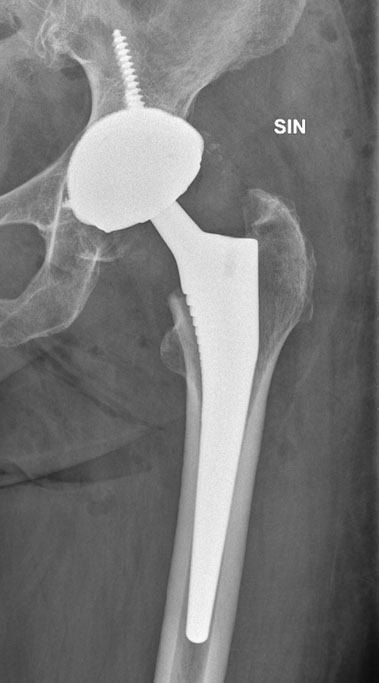

The patient was afebrile with normal laboratory findings except for a slightly elevated alkaline phosphatase. Arthrocentesis showed a nonviscous fluid with a normal leukocyte count with only 30% polymorphonuclear leukocytes. Infectious etiology was further excluded by negative bacterial cultures both in the joint aspirate obtained preoperatively and peroperatively by multiple biopsies. The patient was successfully operated with a single-stage total hip arthroplasty and recovered without any complications (Figure 3). The diagnosis of rapid destructive osteoarthritis was made after clinical exclusion of other causes of destructive arthropathy.

Figure 3: Postoperative radiography after hip arthroplasty with a cementless dual mobility cup (Trident TritaniumTM acetabular shell, Stryker) and a cementless hydroxyl-apatitecoated femoral stem (Corail®, DePuy).